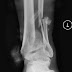

Miał być artykuł o pierwszym wyjeździe w trasę, a tu minęło pół roku i nic nie napisałem. Działo się w tej pierwszej trasie tak dużo, że nie sposób było wyciągnąć aparatu, a co dopiero o napisaniu kilku słów. Moja pierwsza trasa miała być tygodniowym wypadem - Austria i Czechy. W ostatnim dniu ładowałem się w Czechach, by z towarem wrócić już do Polski i do domku. Cała ta sytuacja była dziwna. Po załadowaniu auta, okazało się, że auto zostało przeładowane, tak dość solidnie, wyjaśniłem to z punktem ładunkowym i jakże się okazało, że był błąd na fakturze. Tak wszystko działo się szybkiej atmosferze, firma nie znalazła bałwana, który zabrałby wszystko naraz - trzeba było ściągnąć połowę towaru z auta. Zapiąłem towar pasami i ześlizgnąłem się z paki samochodu jakoś tak niefortunnie, że spadłem na posadzkę, łamiąc przy tym nogę. Leżąc na ziemi pamiętam widok wystającej kości, uwierzcie mi, wolałbym jej nie widzieć na wierzchu. Wyjąłem telefon z kieszeni spodni, pierwszy telefon wykonałem do żony - kochanie złamałem nogę, zadzwonię jak coś więcej będzie wiadome, drugi telefon do szefa - Marcin, spadłem z paki, złamałem nogę, karetka w drodze. Szczerze mówiąc, to chyba mój organizm wygenerował na tyle adrenaliny, że nie czułem żadnego bólu. Owszem próbowałem podnieść lekko nogę, ale jak spostrzegłem, że stopa bezwładnie opada, trzymając się jedynie na skórze, to zaniechałem dalszych prób. Sprawdziłem tylko czy mogę poruszyć palcem u nogi, taka myśl mnie przeszła, czy ścięgna i nerwy całe, palec na szczęście się poruszył w bucie.

Gdy dojechaliśmy do szpitala, pierwszym pytaniem było, czy jestem ubezpieczony, oraz numer ubezpieczenia, jak by to było ważniejsze od mojej nogi. Ubezpieczony byłem, ale na numer się czeka miesiąc czasu, a ja miałem wypadek dnia 5. Dobrze, że język czeski jest na tyle podobny do naszego ojczystego, że jakoś się dogadałem. Ku mojemu zdziwieniu, w szpitalu czeskim, 70 km za Pilznem, pracował polski pielęgniarz, który jak się okazało jest też szpitalnym księdzem. Co za zbieg okoliczności. W szpitalu na dzień dobry zrobiono mi kilka zdjęć, lekarz naciągnął nogę by kość się schowała, oraz jednym szwem zaszył dziurę. Obłożył gazikami i powiedział, że jutro operacja. Pięknie pomyślałem. Nie zdawałem sobie sprawy z tego, jak źle to wyglądało. Dostałem kroplówek kilka i odwieźli mnie do sali. Sala była dwu łóżkowa, byłem sam, na szczęście przy oknie. Telewizor na ścianie, pilot, bez żadnych monet, czy żetonów, toaleta z prysznicem w pokoju. Emocji wiele jak na jeden wieczór. W jednej krótkiej chwili, może cały świat planów się zawalić. Tej nocy nie zmrużyłem oka, nie chodziło o ból, bo prawie go nie odczuwałem, jedynie ten mętlik myśli, co będzie dalej.

Następnego dnia zaczął się ruch o 6 rano, pierw salowe - poranna higiena, zmiana pościeli.  Jak się okazało pościel zmieniali codziennie rano, a w szpitalu przeleżałem równiutki miesiąc. O 8 wizyta lekarzy, taka grupa z ordynatorem, krótka rozmowa, dobrze że lekarze i ordynator dobrze mówili po angielsku. Operacje przygotowują na południe, teraz seria badań. Pierw zabrano mnie na tomograf, później do lekarza od serca, skoro operacja to i narkoza, trzeba sprawdzić EKG i wywiad. Z EKG prosto na sale operacyjną. Jak się dowiedziałem po operacji, ściągali do mnie chirurga z Pragi, jakiegoś specjalistę od trudnych złamań, jak szukałem w Internecie zaliczał się do pierwszej trójki najlepszych chirurgów w Czechach. Operacja trwała trzy godziny. Dostałem blokadę w kręgosłup, a na sali zostałem uśpiony. Z najnieprzyjemniejszych odczuć w czasie operacji to przebudzenie się podczas niej. Dosłownie odzyskałem świadomość podczas operacji, po prawej mojej stronie monitor z rentgenem, hałas wkrętarki i drżenie i szarpanie nogi, na ekranie widać jak wiertło przewierca kość. Trwało to chwilkę, jak tylko zobaczyli, że mam otwarte oczy i ruszam głową, to od razu mnie uśpili dalej, jednak na same wspomnienie, wolał bym tego nie widzieć. Po całej operacji ocknąłem się w chwili jak zaczęli ściągać te wszystkie materiały, co mnie odgradzały od chirurgów. Okazało się, że dostałem zespolenie zewnętrzne.

Gips musiał być rozkrojony do zmiany opatrunków i takim to sposobem miałem taką muszelkę na nodze, owiniętą bandażem elastycznym. Poruszanie stało się wygodniejsze, już nie kopałem się w tą konstrukcję. Minusem tego było tylko waga gipsu, konstrukcja była lżejsza. Po tej drugiej operacji zaczęła mi bardziej puchnąc stopa. Wcześniej jak miałem konstrukcję, to gdy opuściłem nogę, to po prostu kapało mi z pięty, gdzie był ten wystający pręt. Potrafiłem dość sporo nakapać w czasie samego jedzenia obiadu, teraz gdy nie było żadnej dziury, te płyny po prostu zbierały się pod skórą. Stopę miałem prawie dwa razy większą od prawej. Na trzeci dzień już było dobrze, na tyle dobrze, że wieczorem oglądając film, w przerwie na reklamy po prostu wstałem z łóżka i prawie się wywróciłem. Nic mnie nie zabolało, jedyne co to jak bym stanął na piłce, przechyliłem się i dobrze, że złapałem się łóżka. Sąsiad się wystraszył, krzyknął - co ty robisz, a ja zbladłem, ze strachu że coś się tam mogło poruszyć. " Skoczyłem " z " ambonką " na korytarz blady jak ściana, mówię pielęgniarce, że stanąłem na nodze. W chwili był u mnie lekarz, mówiąc że nic się powinno stać, bo gips i blachy, ale rano zleci kontrolne zdjęcie RTG. Tak jak powiedział tak się i stało, już o siódmej rano zabrali mnie na zdjęcie, tak by na obchód lekarzy wszystko było wyjaśnione. Naprawdę opieka i podejście do pacjenta w Czechach jest na wysokim poziomie. Na czwarty dzień od drugiej operacji przestałem potrzebować jakichkolwiek leków na boleści, a czas w szpitalu zaczął mi się bardzo dłużyć. Pogoda zaczęła się pogarszać, często padało, jedyną rozrywką były odwiedziny księdza, czy jakiegoś pacjenta. Wtedy zawsze przynosili mi dobrą kawę z kawiarni, ta z automatu bardzo mi się znudziła, dobra była, jednak miała taki specyficzny smak automatu kawowego. Taka świeża aromatyczna z kawiarni to jak święta dla mnie. Coraz lepiej poruszałem się też o kulach, już nie musiałem zabierać wszędzie " ambonki ". Czas mijał a ja czułem się coraz lepiej, w szpitalu spędziłem równiutki miesiąc. W następnym artykule opiszę wam mój powrót do Polski, oraz pierwsze zderzenie się inną rzeczywistością.